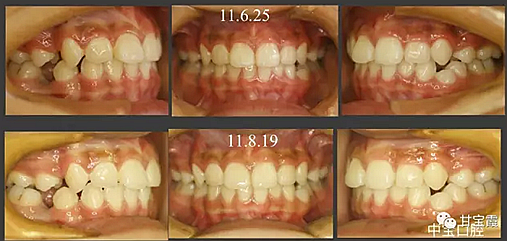

病例一

有一個七歲的小女孩,在替牙時媽媽發(fā)現(xiàn)孩子新長的牙不整齊,有一顆長到里面了,上下頜中線也不對稱,很著急就來到門診看牙。

經(jīng)過我臨床檢查和X線的診斷,決定早期干預(yù),每三個月定期復(fù)診檢查一次,并拔掉了幾個乳牙和四個恒牙,正畸專業(yè)叫序列拔牙。

5.png

經(jīng)過三年零九個月的看護,最終戴上了固定矯治器,但是大家不難發(fā)現(xiàn),孩子的牙齒已經(jīng)排齊,上下中線也基本對齊,面型也好看多了,這樣矯正就變得簡單,療程自然縮短,孩子也不遭罪了。